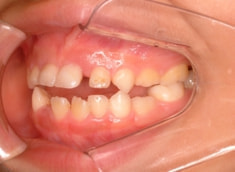

治療前